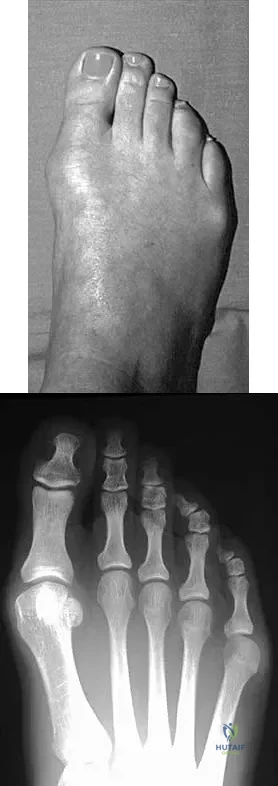

A 28-year-old woman has a moderate hallux valgus deformity and a prominence of the medial eminence. She can participate in all activities and reports that she could wear 3-inch heels in the past, but she now notes medial eminence pain even while wearing a soft leather flat shoe with a cushioned sole. She requests recommendations regarding surgical correction. Examination reveals a 1-2 intermetatarsal angle of 10 degrees. A clinical photograph and radiograph are shown in Figures 13a and 13b. What is the best course of action?

Based on her symptoms and prior shoe wear modifications, the treatment of choice is surgical correction of the hallux valgus with a chevron osteotomy. There are no data to support the use of a custom orthosis to delay the progression of a hallux valgus deformity. Steroid injection would only risk infection, as well as joint and capsule damage. Extra-depth shoes are an option; however, the patient is interested in surgical options. Chou LB, Mann RA, Casillas MM: Biplanar chevron osteotomy. Foot Ankle Int 1998;19:579-584. Coughlin MJ: Roger A. Mann Award: Juvenile hallux valgus. Etiology and treatment. Foot Ankle Int 1995;16:682-697.